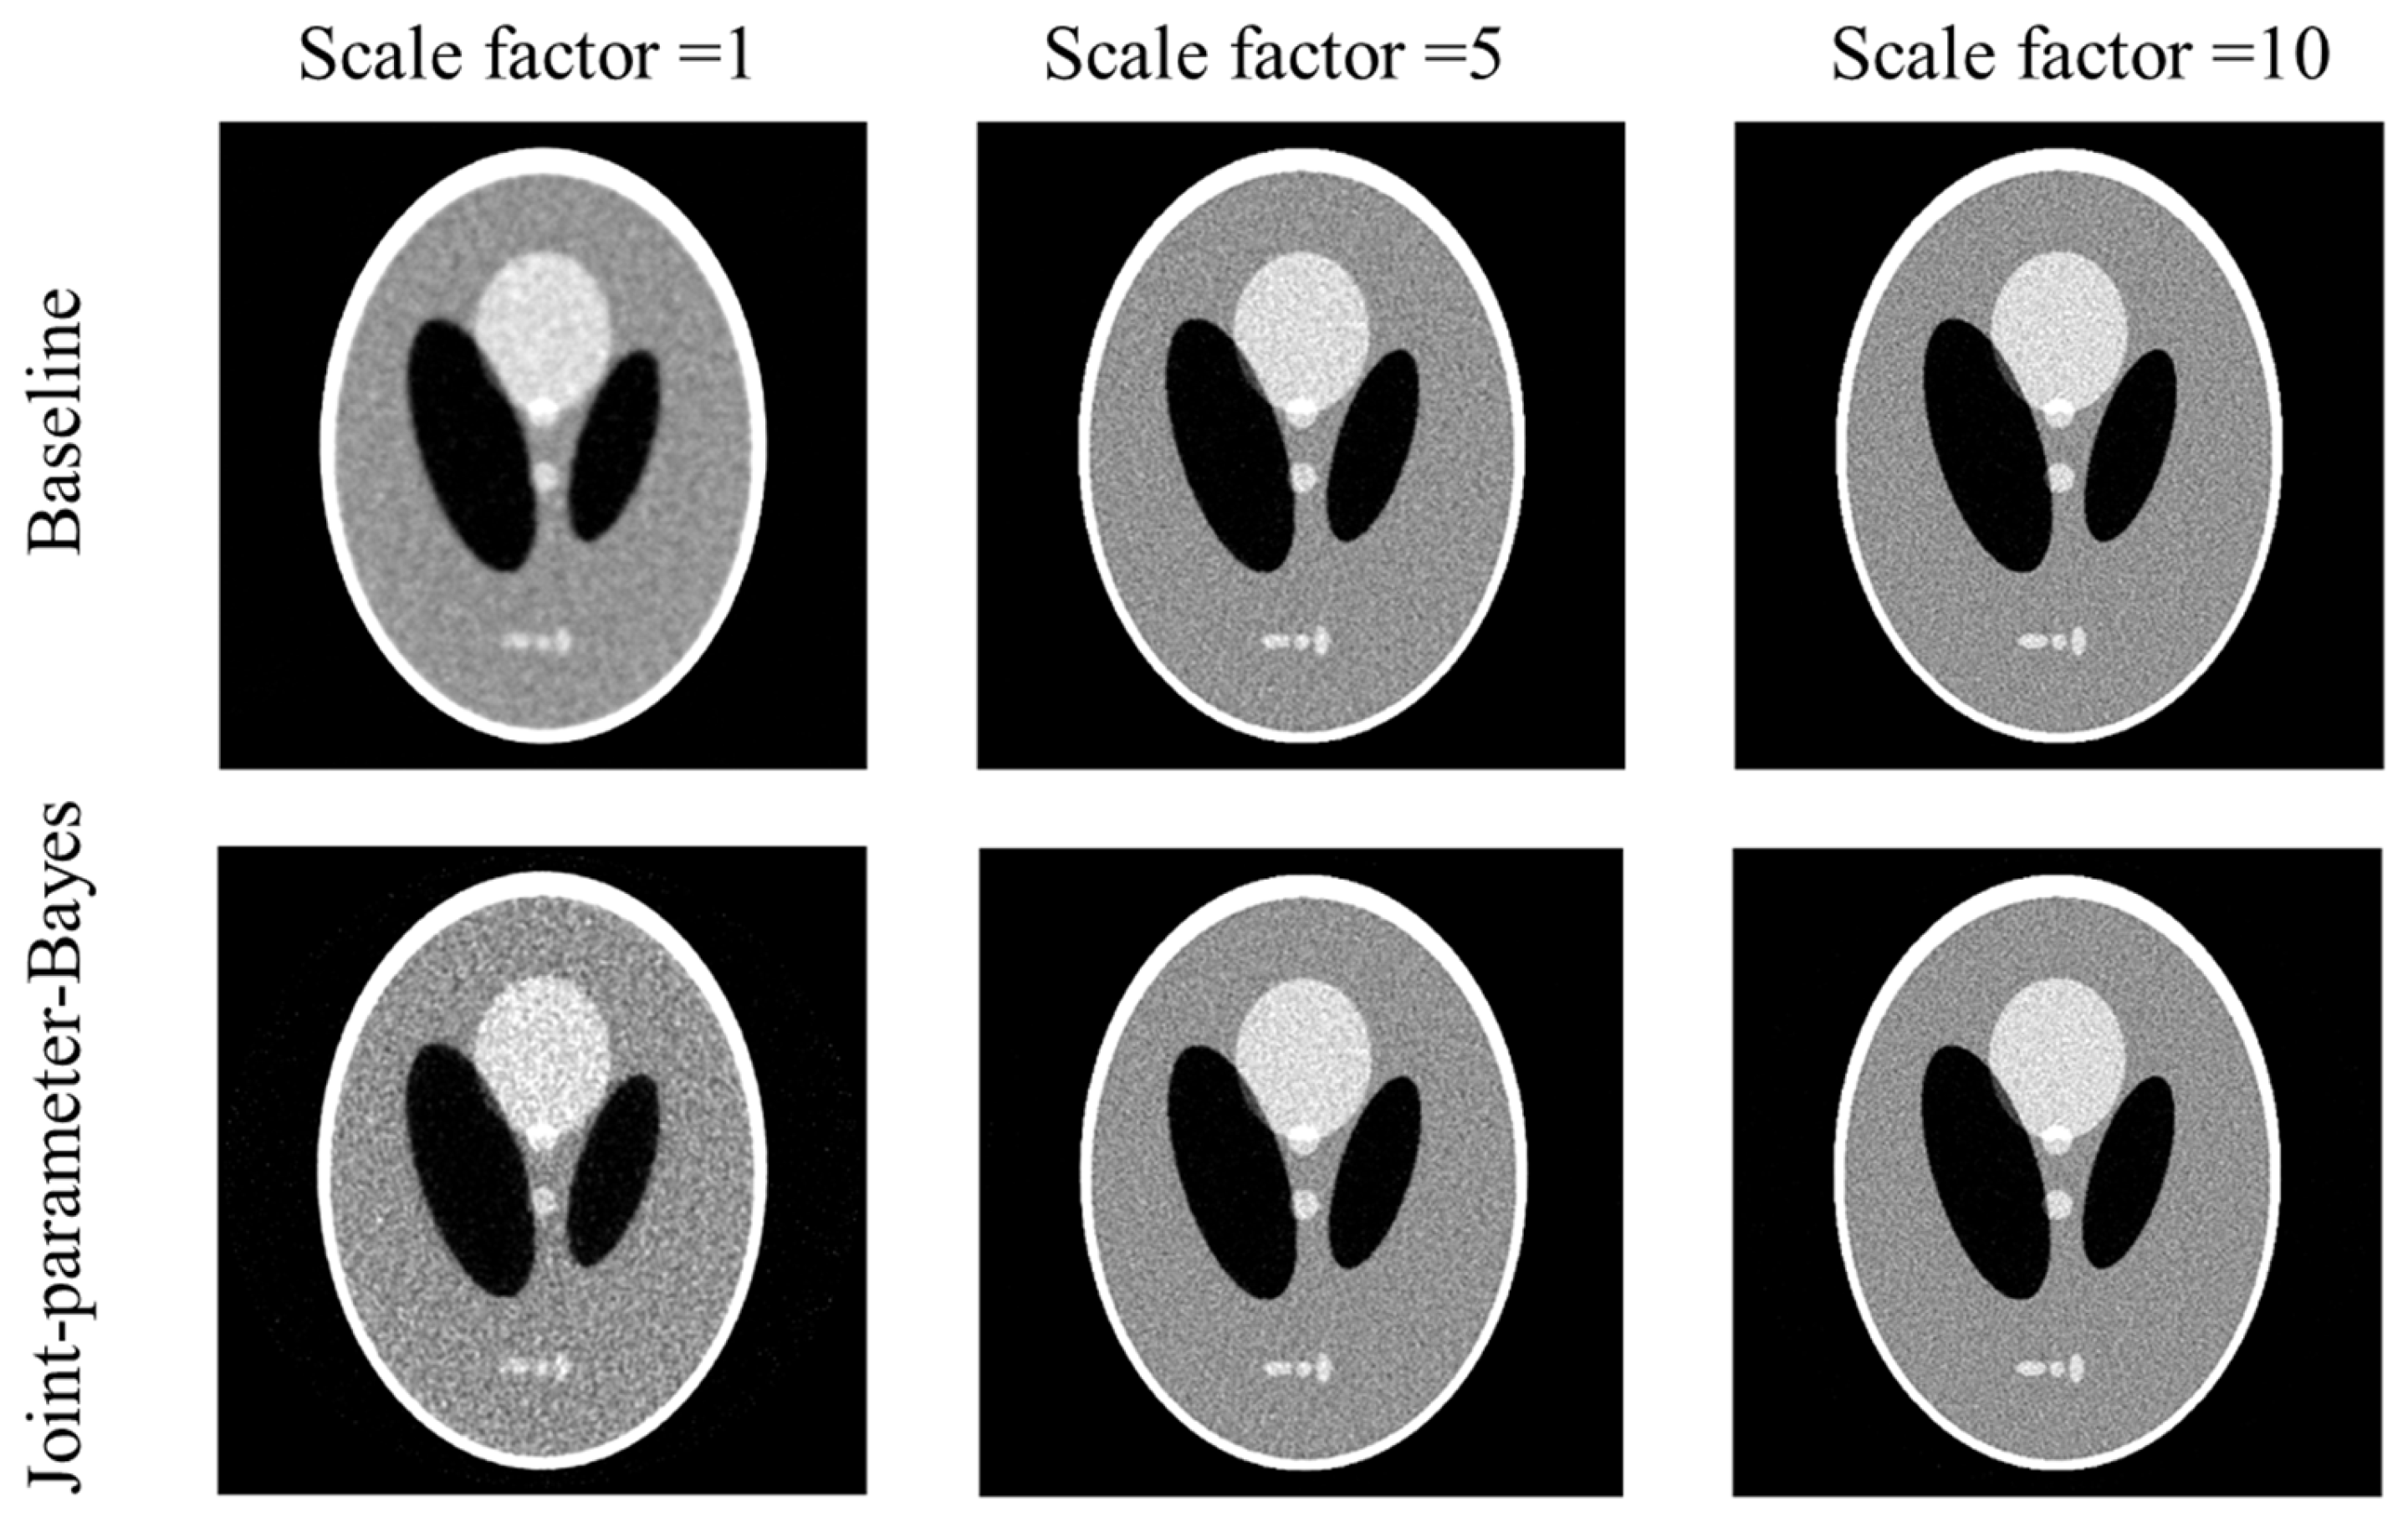

As we know, is the variance factor from the measurement. The element value range might vary from different modalities. For example, in the simulation, for the Poisson-like signal-dependent noise to post-log sinogram data, and for the Poisson noise to the pre-log transmission data. Therefore, it is useful to know whether the normalization of matrix will affect the performance of the joint-parameter-Bayes method. Figure 9 presents the reconstructed images for without (upper) and with normalization (lower) by on the Poisson-like signal-dependent noise to post-log sinogram data. The scale factor is 1. Comparable reconstructed images are obtained. The estimated parameters follow the same pattern with linear scaling strength. This observation agrees with our expectation that even though the magnitude of are scaled due to normalization, the fidelity strength and prior strength will also be scaled by the same degree. Therefore, the results would not be affected.

Figure 9.

Performance of joint-parameter-Bayes images for without (upper) and with normalization (lower) by . The CT image display window is [0, 0.035] mm−1.